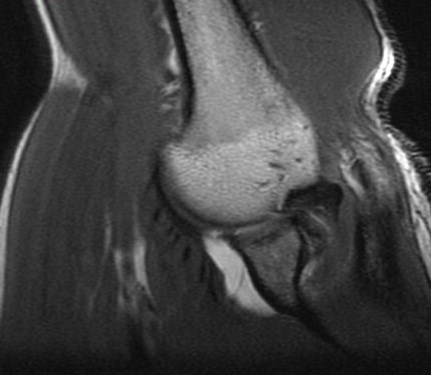

19 y/o college pitcher. Pain with throwing.

Posterior superior glenoid bone build up from chronic peel back stress. There are superimposed acute edematous changes. Abstract from Burkarts article describing it is included. Reference article.

Posterior Peel Back Lesion of Internal Impingement